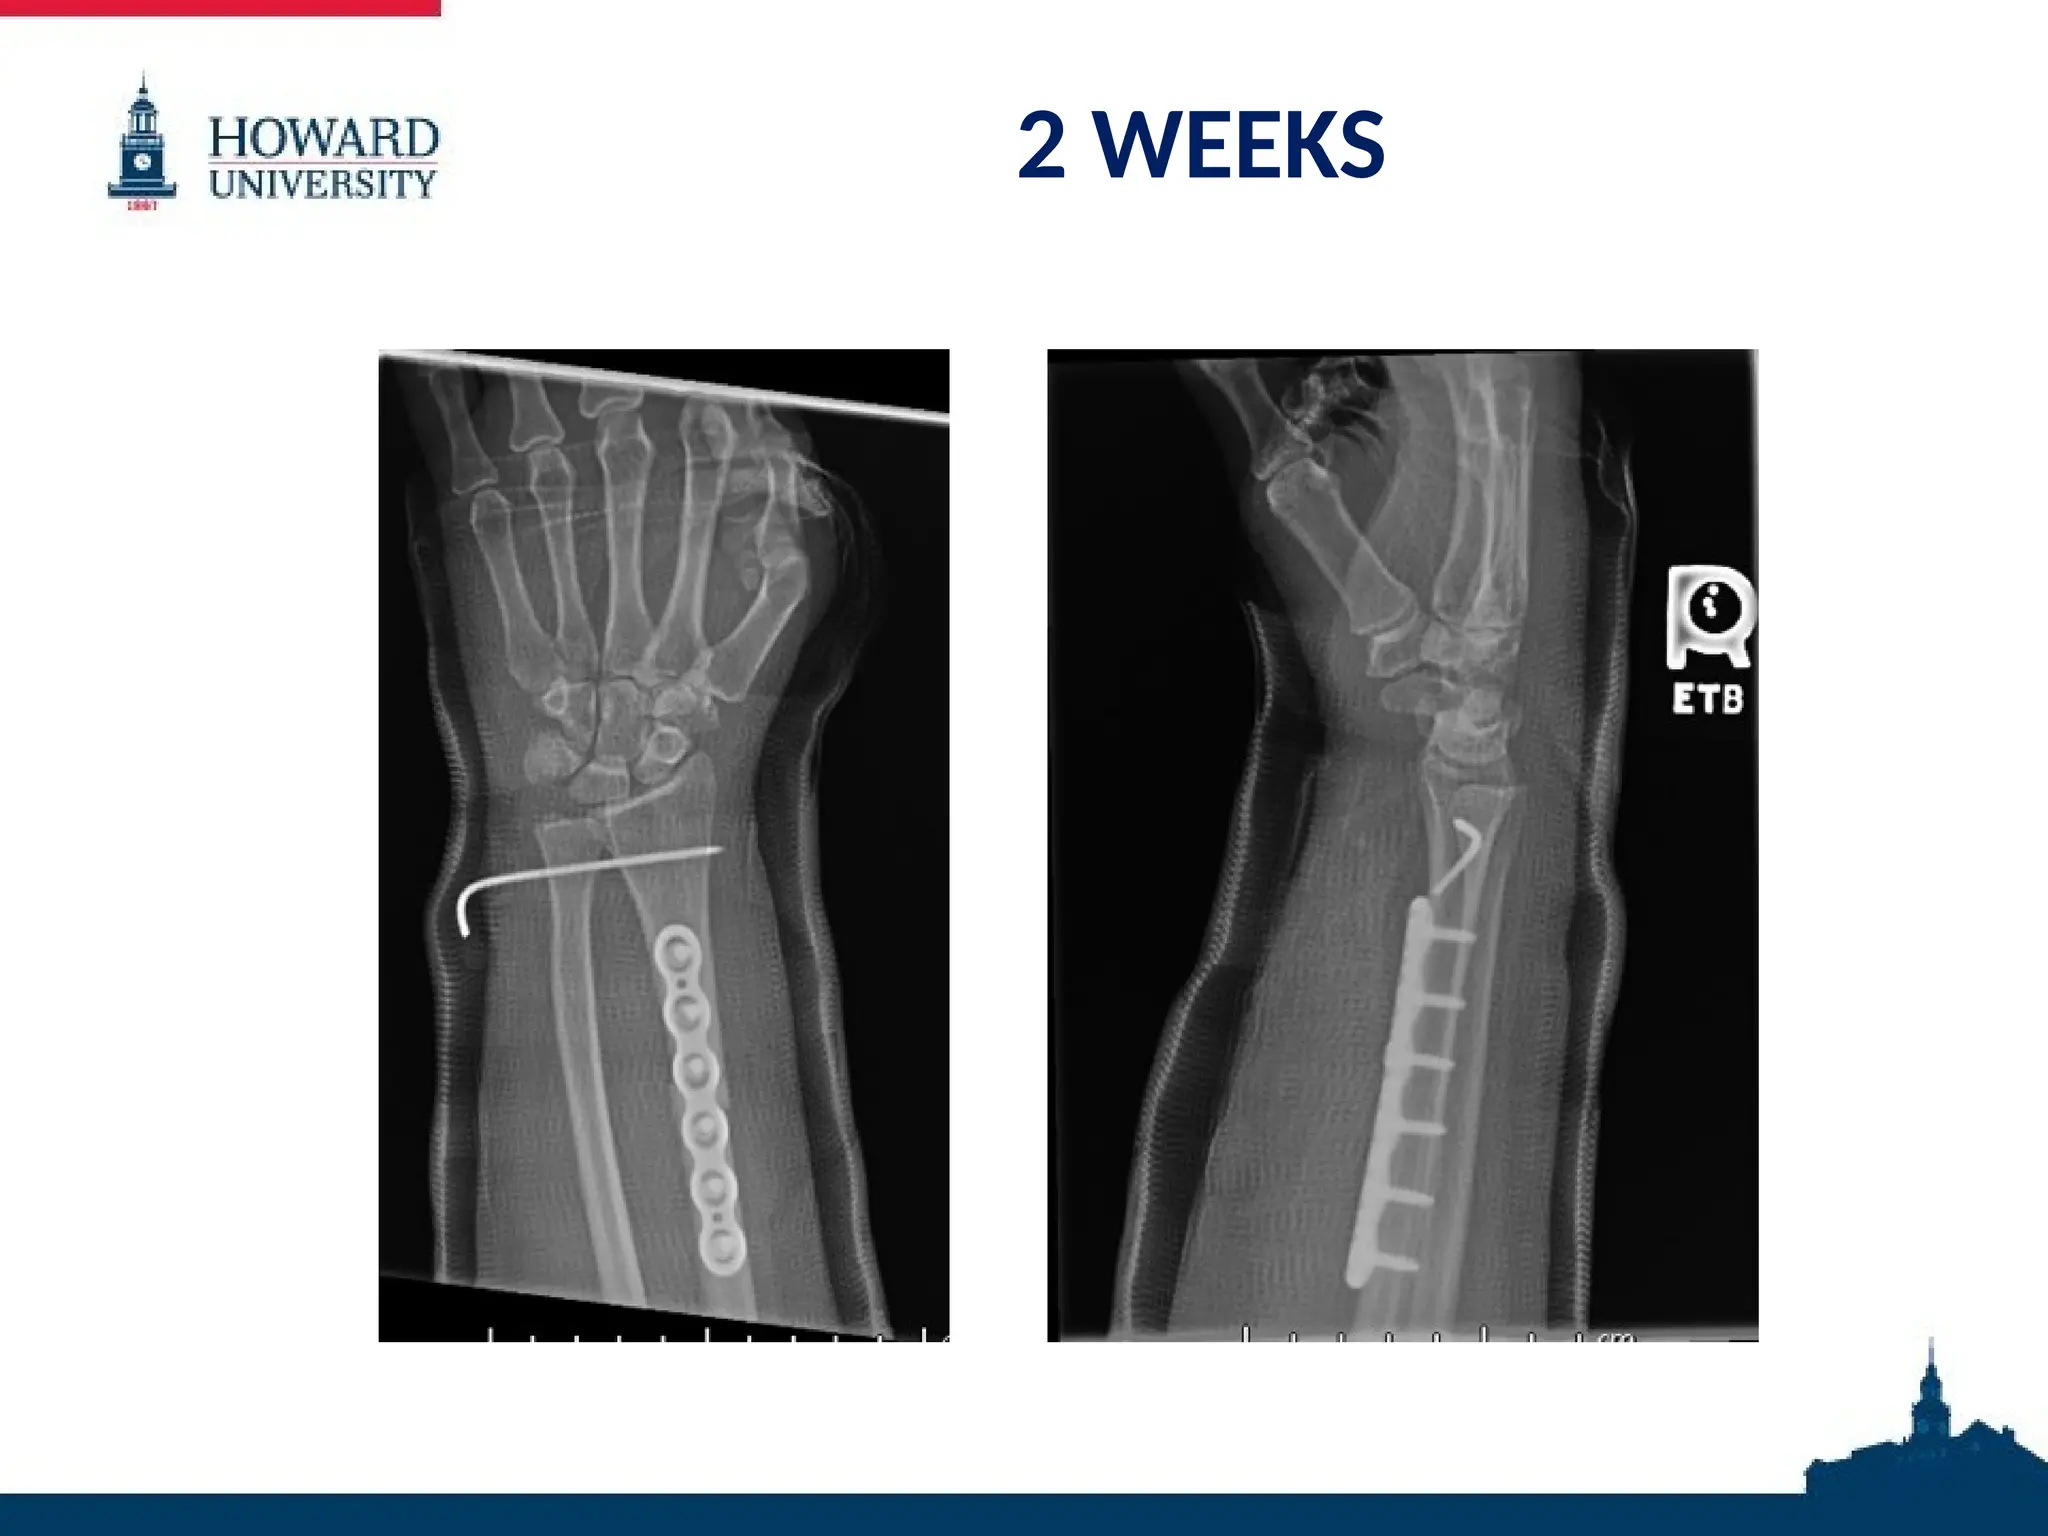

2 WEEKS

POST-OPERATIVE COURSE 2 weeks: •Incision c/d/i • Pain controlled • Long arm cast placed

• 33.